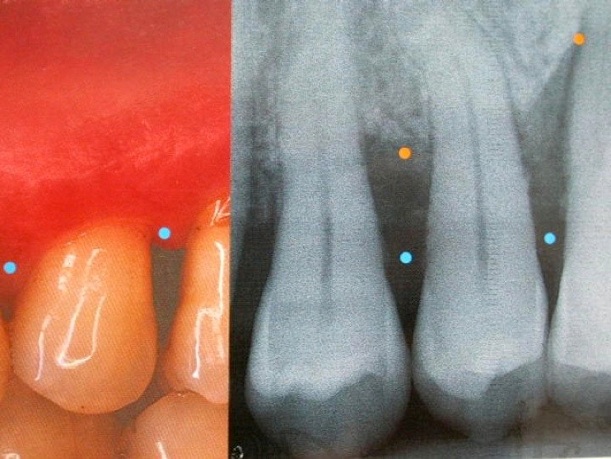

-les gencives saignent au brossage ou spontanément

-les gencives sont rouges violacée ( signe d’inflammation chronique) à la place d’avoir la couleur rose

Gingivites = inflammation gingivale sans atteinte osseuse , complètement réversible à l'état sain par une reprise correcte de l'hygiène dentaire et détartrage. Les saignements au sondage ou au brossage dentaire sont provoquées par les bactéries contenues dans la plaque dentaire et le tartre.

Parodontite = perte d’attache ( os , gencive, ligaments , cément radiculaire) , partiellement réversible par traitement non chirurgical ( détartrages et surfaçages radiculaires ) ou chirurgical et reprise correcte de l'hygiène dentaire et maintenance parodontale régulière . La perte osseuse horizontale est irréversible. On peut régénérer l’os partiellement dans le cas des lésions osseuses verticales.

1.Pour le parodonte fin, la résorption de l’os est accompagné par une récession gingivale, avec l’exposition de la racine